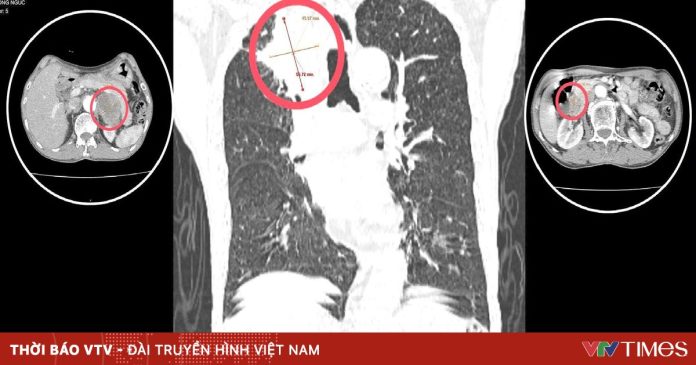

Sau khi thăm khám và làm các cận lâm sàng cần thiết, người bệnh được phát hiện có khối u phế quản phổi phải, theo dõi u ác của phế quản phổi và khối u tuyến thượng thận 2 bên. Người bệnh được bác sĩ tư vấn và chuyển tuyến điều trị thích hợp.